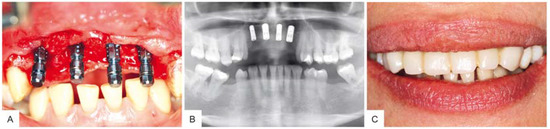

4. Results